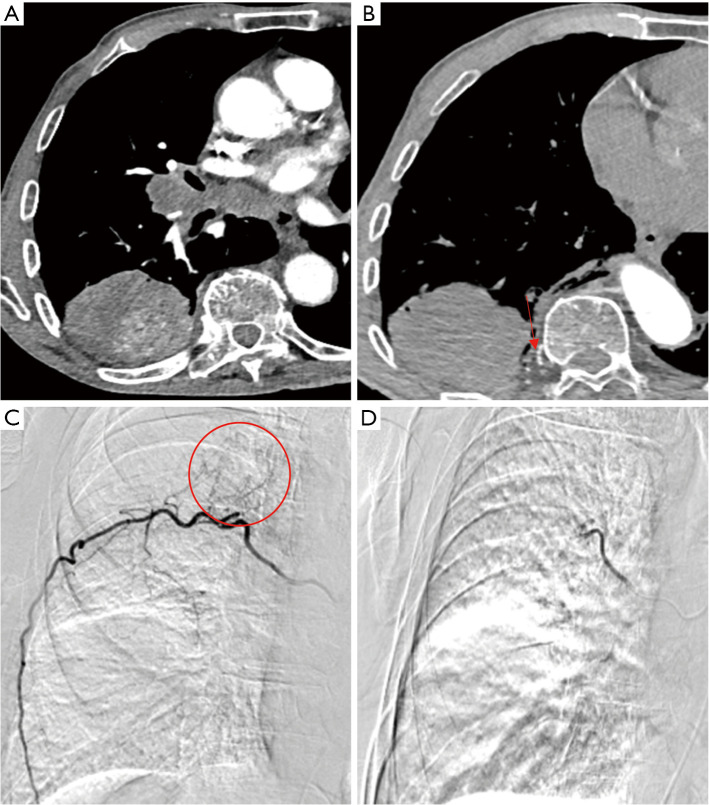

Abstract Image